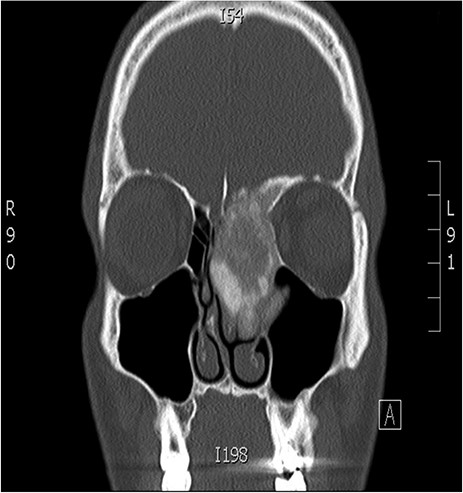

A 34-years-old man presented with left-sided facial pain, headache and nasal obstruction for a long duration, with no history of bleeding per nose, nor blurring of vision. Upon examination, there was a large left nasal cavity bony outgrowth pushing the middle turbinate and pushing the nasal septum to the right side (Fig. 1). CT scan of the paranasal sinuses showed a large mass centered in the left anterior ethmoid sinus, the mass measures 3.7 × 2.9 cm (trans-axial) (Fig. 2) and 3.7 × 5.2 cm (coronal) (Fig. 3), it has a heterogeneous density with calcified and soft-tissue component. The calcified component is in the periphery with central soft tissue density. The mass resulted in remodeling of adjacent bones with nasal septal deviation to the right, it extended superiorly to involve the frontal sinuses as well as invading the left cribriform plate and intracranial extension (Fig. 4), it extended inferiorly displacing the medial wall of the left maxillary antrum. The medial aspect of the mass caused remodeling of the medial wall of the left orbital cavity with bulging and displacement of the medial rectus muscle. The mass resulted in obstruction of the left frontal sinus.

Coronal CT image of the sinuses showing a mass encroaching the orbit and skull base.